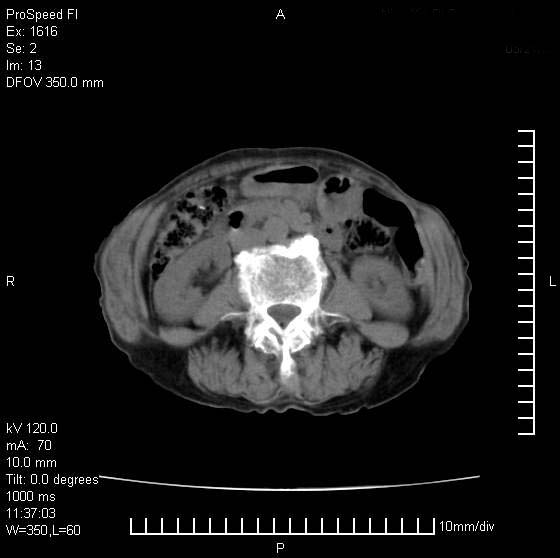

患者无明显临床症状,肝左叶发现一个圆形密度不均的低密度灶,边界较清楚,大小37x45mm,ct值35-70,患者犹豫做增强,如有增强片,我再发上,现先请各位老师会诊.

左肝外叶可见较大圆形低密度影,病灶可见较光整清晰边界,病灶内可见多量条状稍高密度影,右肝前叶亦可见圆形结节状低密度影,边界清晰,密度均匀,考虑1肝多发囊肿,左肝囊肿内出血2肝包虫病3左巨块型肝癌出血合并右肝转移或合并右肝囊肿

左肝外叶可见较大圆形低密度影,病灶可见较光整清晰边界,病灶内可见多量条状稍高密度影

考虑:肝包虫病

肝左叶类圆形低密度影,内可见略高密度影,边界清晰周边可见环形低密度带,考虑肝腺瘤可能,建议增强扫描除外肝血管瘤与肝癌

肝左叶不均匀占位,内有斑片状高密度出血灶,内侧缘似有假包膜,腹主动脉周围及肝门区结构紊乱,似有增大淋巴结,考虑:肝左叶hcc并淋巴结转移。建议增强扫描除外其他。